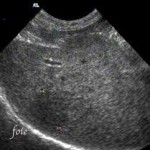

L’échographie est un excellent outil diagnostique des pathologies thoraciques et abdominales et vient en complément de la radiologie.

Elle permet d’évaluer le bon fonctionnement du cœur et de visualiser l’ensemble des organes abdominaux avec précision.